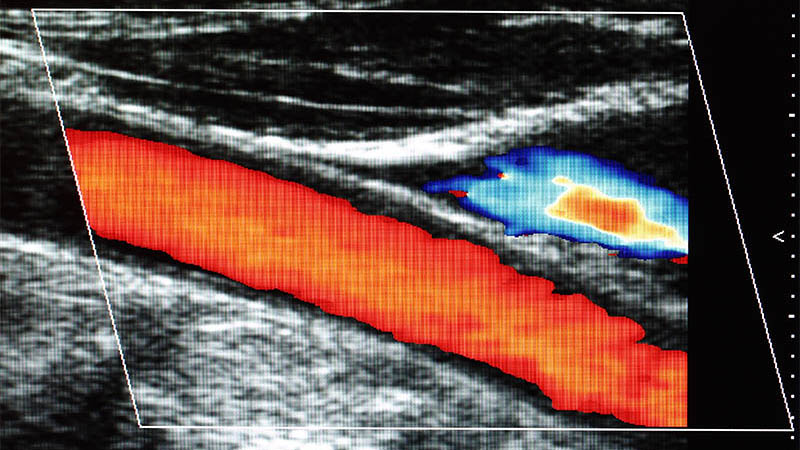

Anatomical variations of the cervical vagus nerve on ultrasonography: a cross-sectional study

Sukhmani Randhawa, Kunwar Pal Singh, Arvinder Singh, Pooja Pal, Sukhdeep Kaur

J Ultrason 2025; 25: 25